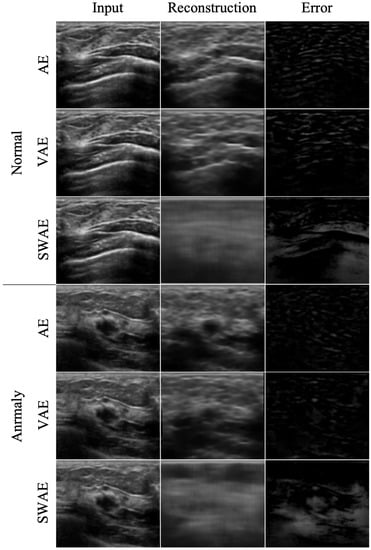

4.2.2. Anomalous Region Detection

To evaluate the anomaly detection performance of the three models, we used three indicators, Dice, TPR, and FPR, as described in Section N. The results of detecting anomalous regions by the three models based on an arbitrary threshold of 0.2 are shown in Table 5.

Similarity generally showed low values in the three models. However, they were the lowest in the AE model, and all indicator values showed the highest results in the SWAE model. The SWAE model showed relatively high sensitivity and good performance, but the FPR value was relatively low. Figure 10 shows each model’s anomalous region detection performance.

Figure 10.

Reconstructed result images by models.

The AE model, which has the smallest similarity, sensitivity, and performance values, restored an input very similarly. It can be seen that there is almost no region indicating an abnormality in the case of binary division based on a specific threshold of 0.2. The VAE model restored the input image similar to the AE model, and both the error and binary-split images, and the indicator values, showed similar results to the AE model. The SWAE model shows the most significant result in all three indicator values. The anomalous region is most clearly detected and displayed in the error and binary-split images.